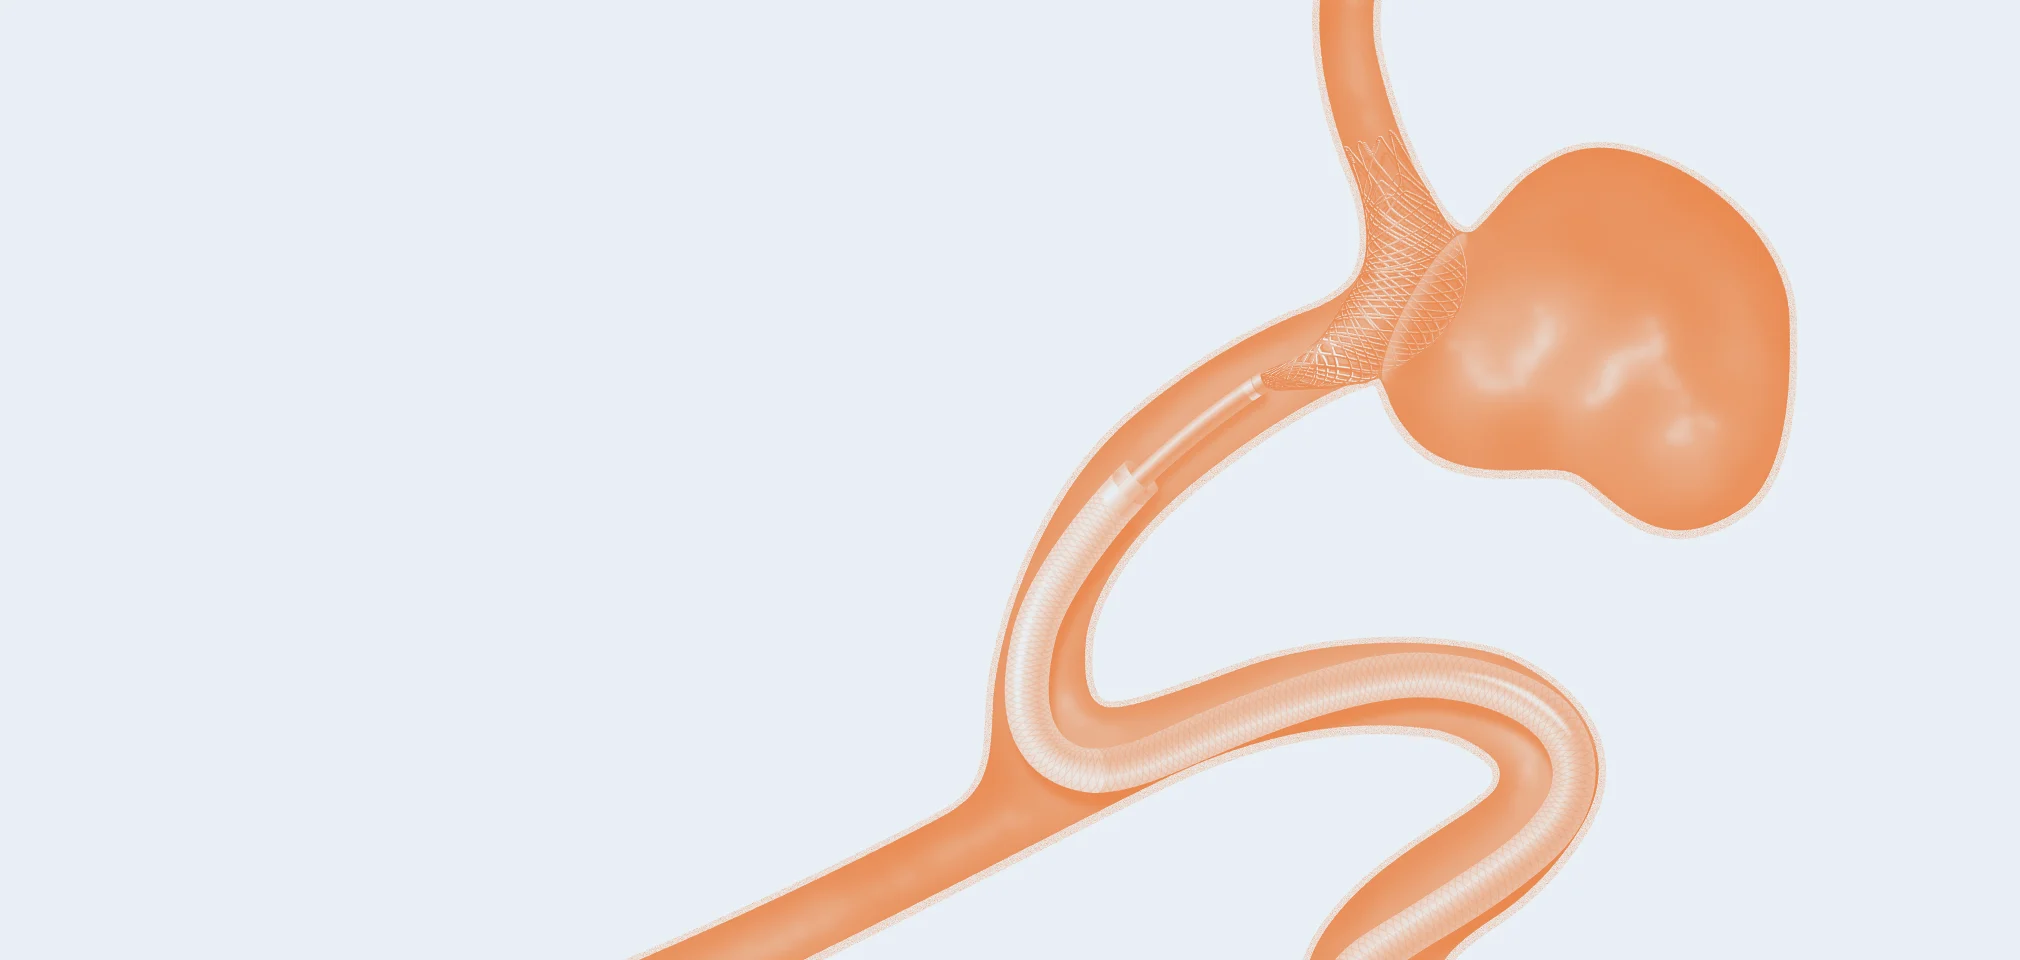

Access products allow doctors to gain access to the treatment area

01 — Guide Catheters

A catheter is a hollow, flexible tube inserted into a vessel to allow the passage of fluids or distend a passageway. Guide catheters are large, robust catheters that allow smaller catheters to pass through and facilitate the placement of various medical devices while providing stability during the procedure.